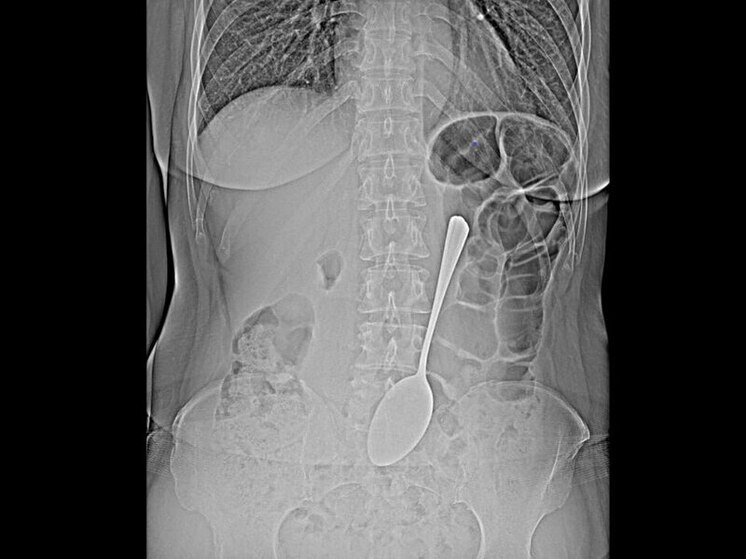

Врачи БСМП в Улан-Удэ извлекли из желудка пациентки столовую ложку

Врачи-эндоскописты Республиканской клинической больницы скорой медицинской помощи им. В.В. Ангапова в Улан-Удэ провели уникальную операцию - они спасли пациентку, которая проглотила столовую ложку.

Инородный предмет успешно извлекли из желудка с помощью эндоскопа и специальных инструментов. Эта современная методика позволила избежать сложной полостной операции, которая потребовала бы длительного восстановления, пояснили в БСМП.

По словам врача-эндоскописта Валентины Бабудоржиевой, подобные случаи представляют серьезную опасность. «Инородные предметы в желудке могут спровоцировать перфорацию его стенки или кишечную непроходимость. Мелкие объекты, например монеты, иногда выходят самостоятельно. Но в случае со столовой ложкой последствия могли быть гораздо серьезнее», — отметила специалист.